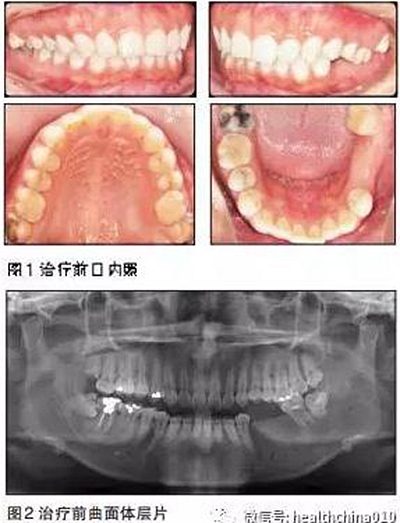

患者女性,29歲。主訴:15年前左下后牙爛牙,在當(dāng)?shù)匮揽崎T診拔除,未給予修復(fù)。

近15年來(lái)患者由于左側(cè)牙齒無(wú)法咬碎食物,一直用右側(cè)后牙咀嚼,自覺(jué)臉型逐漸不對(duì)稱,要求修復(fù)左下后牙恢復(fù)咀嚼功能。體健,無(wú)吸煙史。

患者臉型不對(duì)稱,右側(cè)大于左側(cè)。

牙周情況尚可,有少量牙結(jié)石,牙齦無(wú)明顯紅腫。35、36缺失,25、26過(guò)長(zhǎng),17與47,27與37正鎖牙合,咬合時(shí)26、27的牙尖頂?shù)綄?duì)頜缺牙區(qū)牙槽嵴黏膜上。37、47死髓牙。

全口曲面體層片顯示:35、36缺失,缺牙區(qū)牙槽骨有足夠的骨高度,47未行根管治療,38、48近中阻生,18殘根,28頰面深齲近髓。